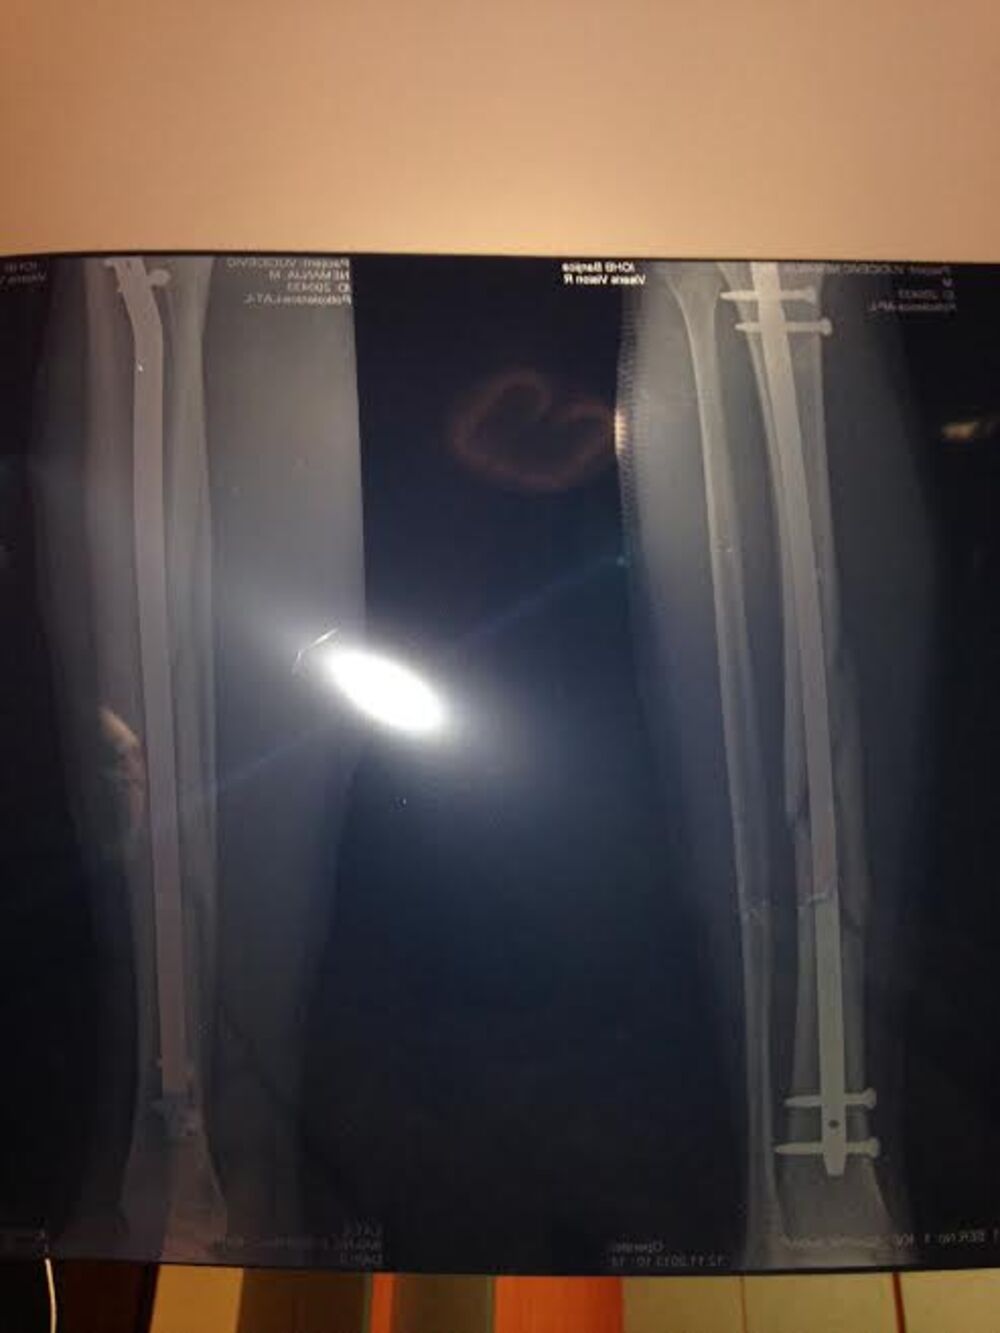

- Desilo se nešto što nisam mogao ni da zamislim. Čitava tribina krenula je da slavi i uleće za mnom na teren i u toj euforiji, neko od njih mi je skočio na nogu, prilikom čega sam zadobio otvoren prelom potkolenice na 4 mesta. Pao sam, a bol koji sam osetio u tom trenutku bio je užasan i mislim da ne bih mogao ponovo da ga podnesem. Jačinu bola najbolje opisuje činjenica da sam se kroz par minuta onesvestio. Sledeće čega se sećam je buđenje u užičkoj bolnici, nakon čega mi je objašnjena težina povrede sa kojom sam se suočio. Kako su mi ortopedi te bolnice rekli, do tada nisu videli sličan prelom, čak ni u najtežim saobraćajnim nesrećama. Jedino što sam u tom trenutku želeo, bilo je da se probudim, jer je sve izgledalo kao ružan san.

Sutradan je Nemanja prebačen iz bolnice u Užicu na ortopediju na Banjici, radi operacije prilikom koje mu je ugrađena šipka u levu nogu. Tu je proveo 24 dana i kako kaže to za njega nije bio ni malo jednostavan period.